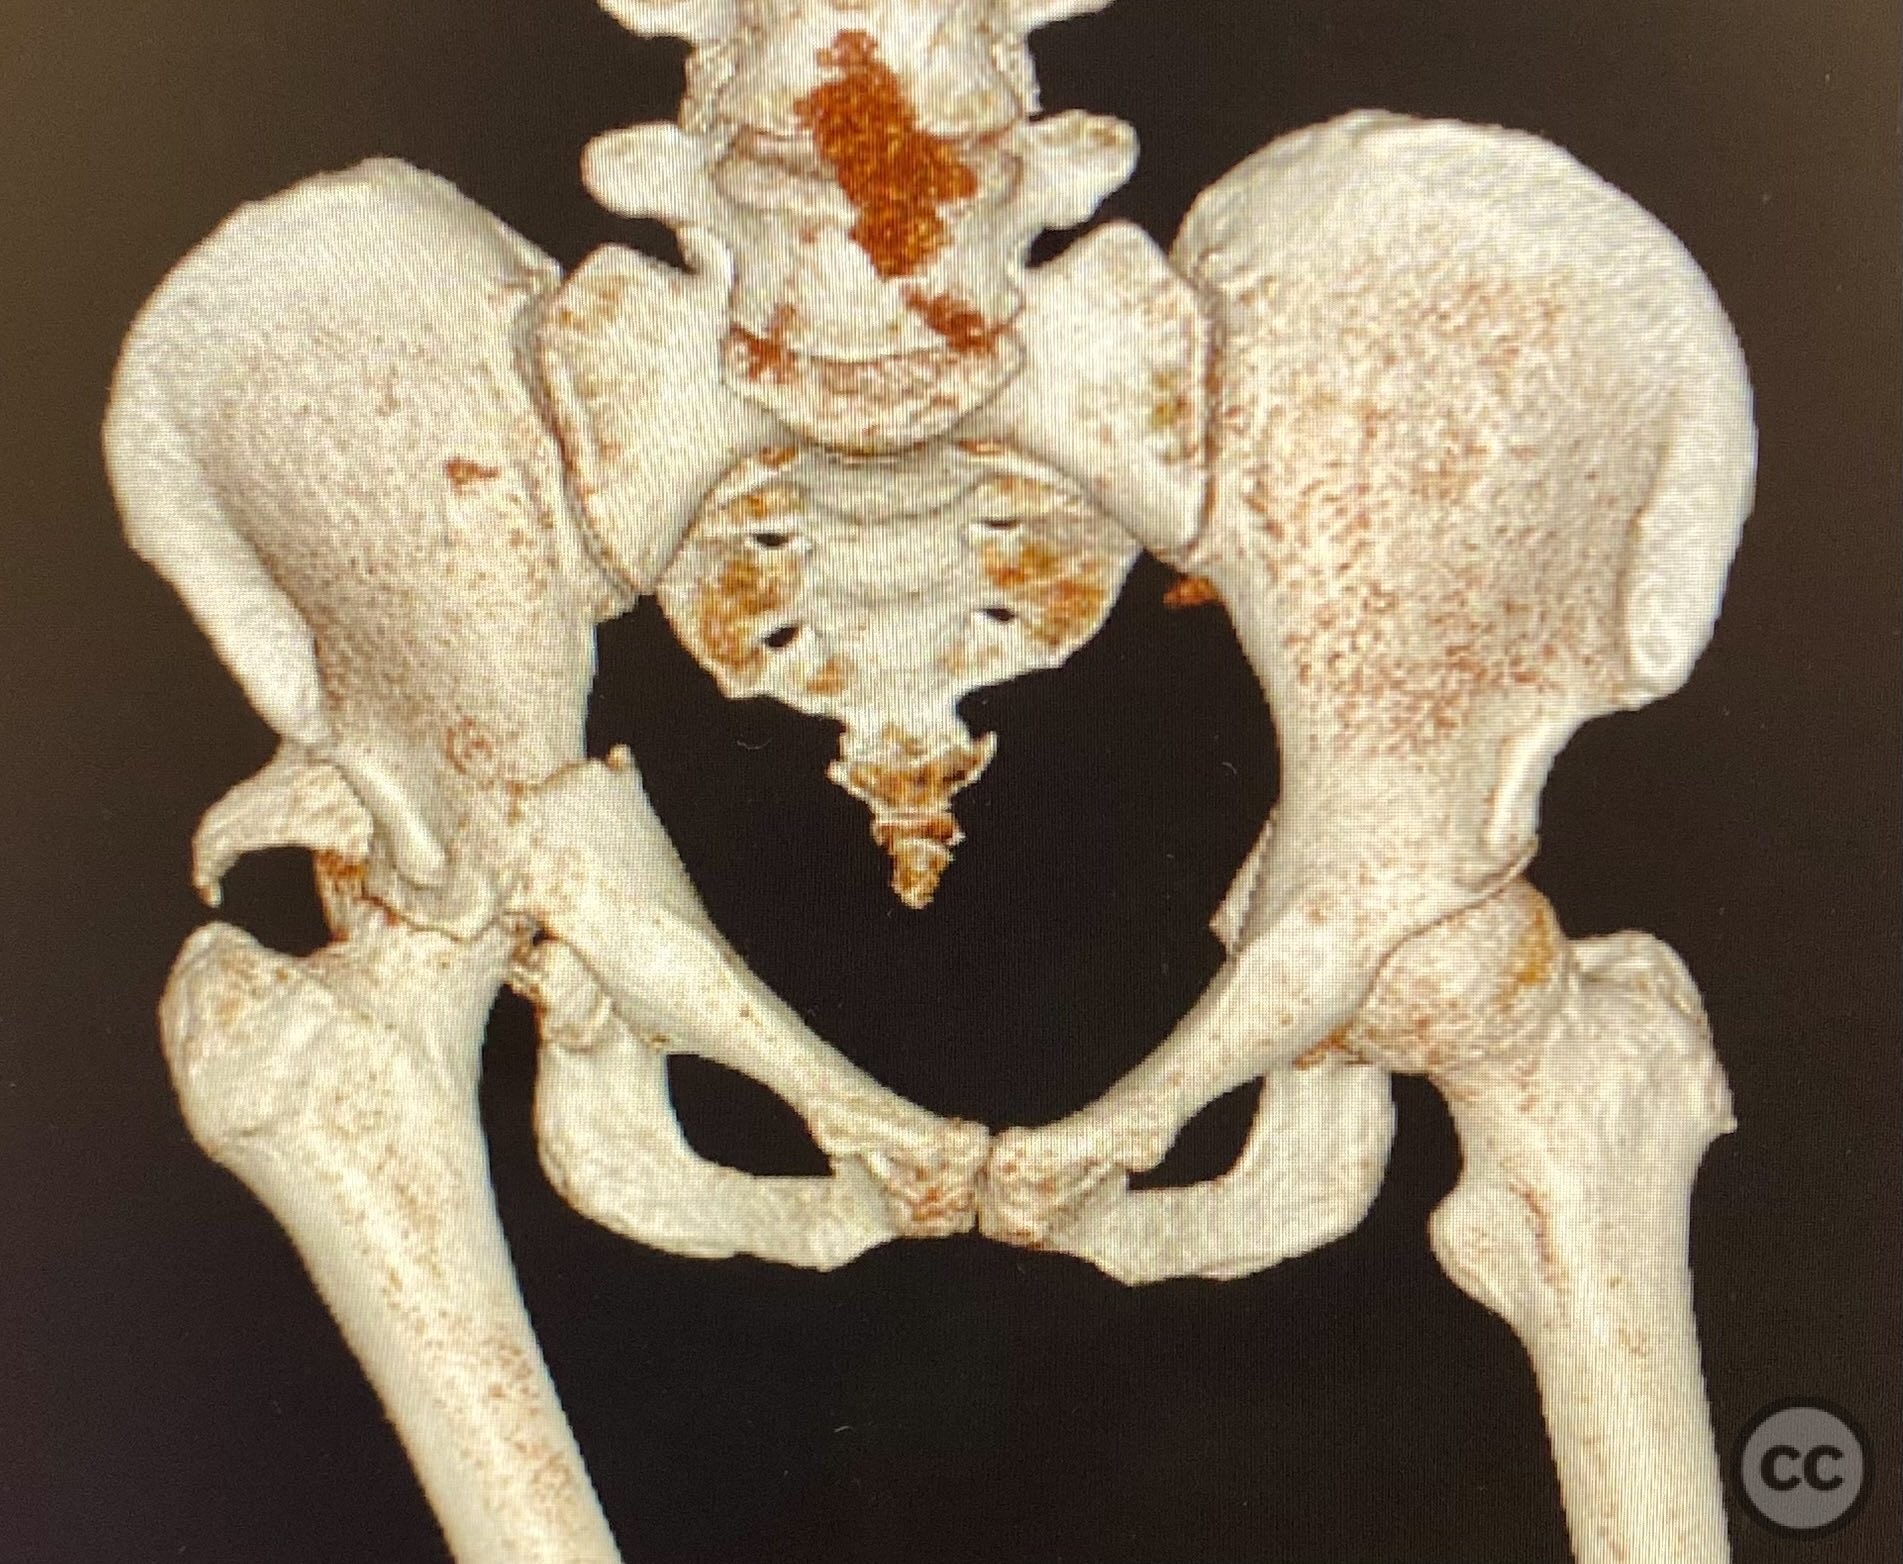

Clinical and radiological findings:  A high-speed motor vehicle collision resulted in a closed transverse acetabular fracture with associated comminuted posterior wall (PW) fracture-dislocation. The femoral head exhibited impaction and comminution, with local cancellous bone crushed and the femoral head itself also sustaining compressive injury from the denser acetabular bone. Neurovascular examination was unremarkable. Initial CT imaging delineated the acetabular fracture planes, displacement, comminution of the posterior wall, femoral head impaction, and absence of soft tissue attachment to the caudal PW fragment.

The transverse fracture was manipulated and temporarily stabilized using a reduction clamp applied across the fracture plane. Under biplanar fluoroscopic guidance, a cannulated cancellous lag screw was percutaneously inserted to achieve interfragmentary compression across the transverse component. The reduction clamp was then removed. Posterior wall fragments were anatomically reduced and stabilized with contoured buttress plates spanning both the posterior wall and providing additional stabilization to the transverse component. Postoperative CT confirmed satisfactory reduction and fixation of both acetabular columns and restoration of articular congruity.